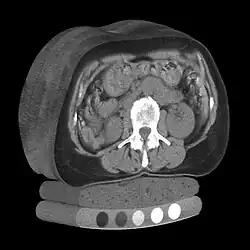

Quantitative computed tomography (QCT) is a medical technique that measures bone mineral density (BMD) using a standard X-ray computed tomography (CT) scanner with a calibration standard to convert Hounsfield units (HU) of the CT image to bone mineral density values.[1] Quantitative CT scans are primarily used to evaluate bone mineral density at the lumbar spine and hip.

In general, solid phantoms placed in a pad under the patient during CT image acquisition are used for calibration. These phantoms contain materials that represent a number of different equivalent bone mineral densities. Usually either calcium hydroxyapatite (CaHAP) or potassium phosphate (K2HPO4) are used as the reference standard.[2]

Originally, conventional 2D QCT used individual, thick CT slice images through each of multiple vertebrae which involved tilting the CT scanner gantry to align the slice with each vertebra. Today, modern 3D QCT uses the ability of CT scanners to rapidly acquire multiple slices to construct three-dimensional images of the human body. Using 3D imaging substantially reduced image acquisition time, improved reproducibility and enabled QCT bone density analysis of the hip.[1]